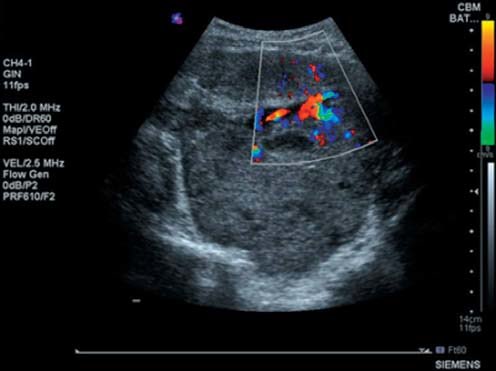

يتم فحص هذه التغيرات عن طريق التنظير الصوتي للورم.

في حالة وجود بعض الدلائل على تغير سرطاني داخل الورم، يفضل ازالته جراحيًا لتفادي انتشار الخلايا السرطانية اثناء الإزالة بالمنظار. الصور التالية هي لأحد الأورام التي تم ازالتها بيد الدكتور أشرف مغربي @AshrafMaghrabi. شكرا له لمشاركتي الصور